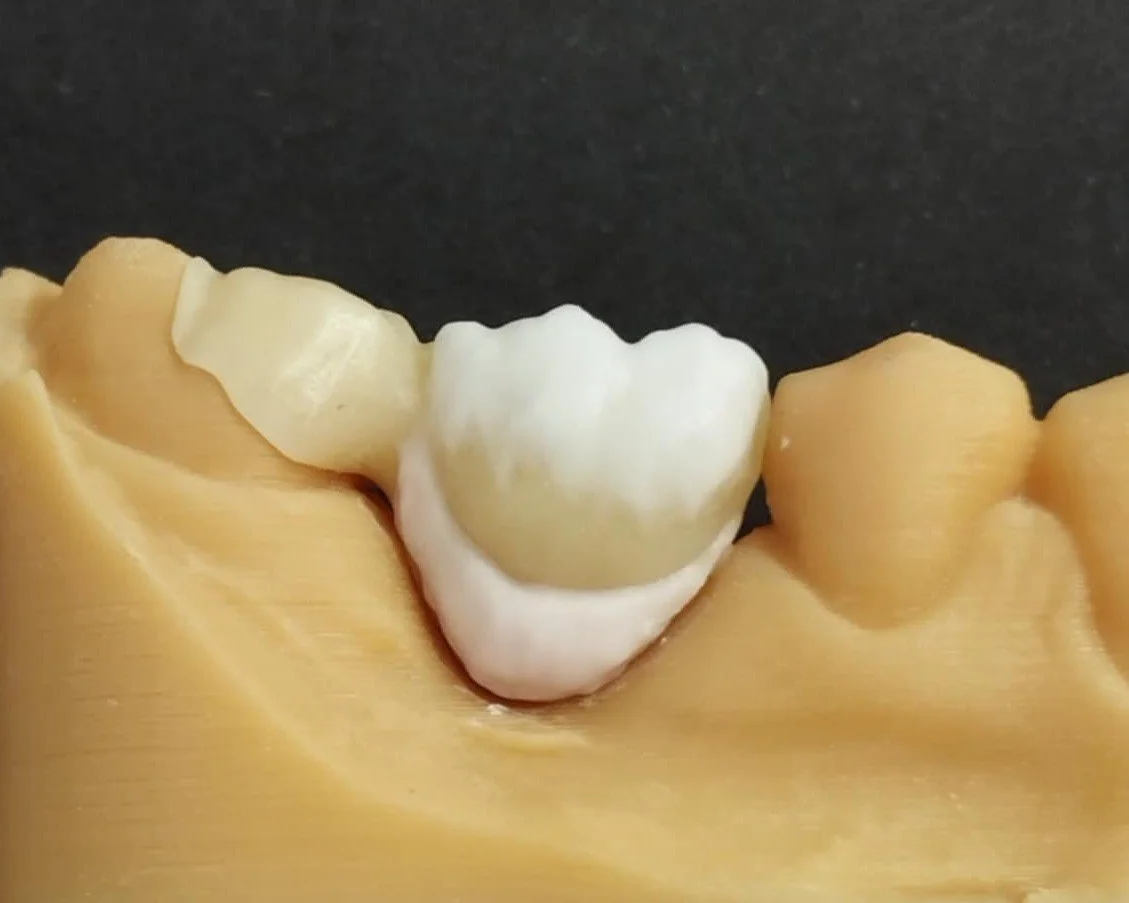

Relativement récents, les bridges collés cantilever postérieurs constituent une alternative fixe, fiable et véritablement minimalement invasive aux implants dans les secteurs postérieurs. Cette thérapeutique qui repose sur des indications bien précises est parfois débattue avec passion sur les réseaux sociaux ou dans les congrès scientifiques. Cependant des études cliniques existent, tout comme des recommandations validées dans des journaux internationaux. Leur succès repose sur des préparations et des principes biomécaniques rigoureux, pourtant simples à intégrer au quotidien. Cette intervention propose un guide clair et opérationnel incluant indications, étapes clés, protocoles d’adhésion et réglages occlusaux pour les mettre en œuvre avec confiance et reproductibilité.